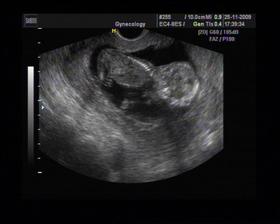

8/10 jsme se byli podívat u paní doktorky, zda testy nelhaly - a ono n e. Puclík měřil 0,37cm a co je důležité - srdíčko už funguje. Táta s Pepínem byli v ordinaci s námi, a když se na monitoru objevilo mimi, tak ho Pepíno pozdravil - udělal mu "ahoj" 🙂 oba nás to s Honzou dojalo. Další kontrola 22/10.